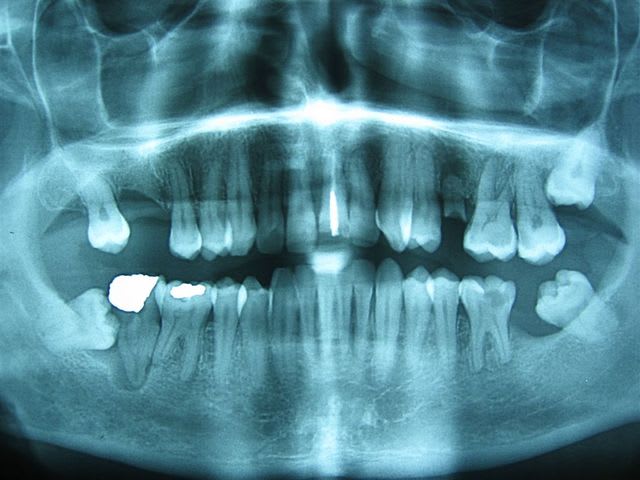

Pour une 46 pas de scan et pas de spix, un OPT une retro et un implant court suffise amplement sauf dans les cas limites. Pourquoi irradier un patient si c'est pas nécessaire ?

A la vue de la pano, je n'appelle pas ça une exo chirurgicale.

Tu n'as sans doute pas eu a donner un seul coup de fraise, tu as jouer un peu avec une curette soit, mais une para-apicale a surement suffit, avec une infiltration "intralig" éventuellement dans la lésion paro-endo.